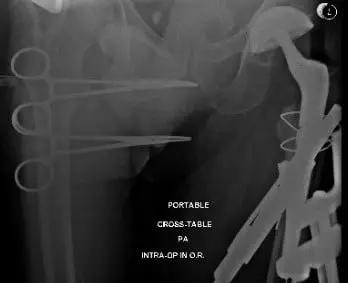

The hip was then relocated and trialed through a physiological range of motion and the hip was found to be stable in all physiological ranges of motion. Intraoperative fluoroscopy was obtained additionally.

The hip was dislocated. The trial components were then removed. Thorough lavage was given. The final proximal body was placed into position along with the final head. The hip was then relocated. The cables were then tightened again and crimped. The cables were then cut.

Intraoperative and postoperative X-ray images showing cables used for fracture fixation and revised long femoral stem.